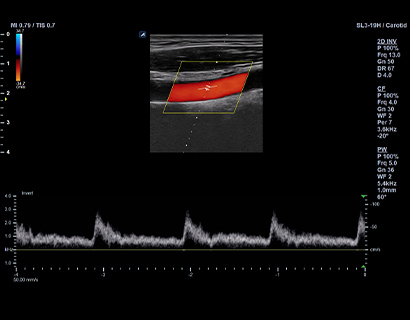

SL3-19H

X+ Crystal Signature™ linear transducer(3~19MHz)

Application:

MSK, Vascular, Small Parts, Breast, TCD, Abdomen, Pediatric, Gynecology, Obstetrics, EM